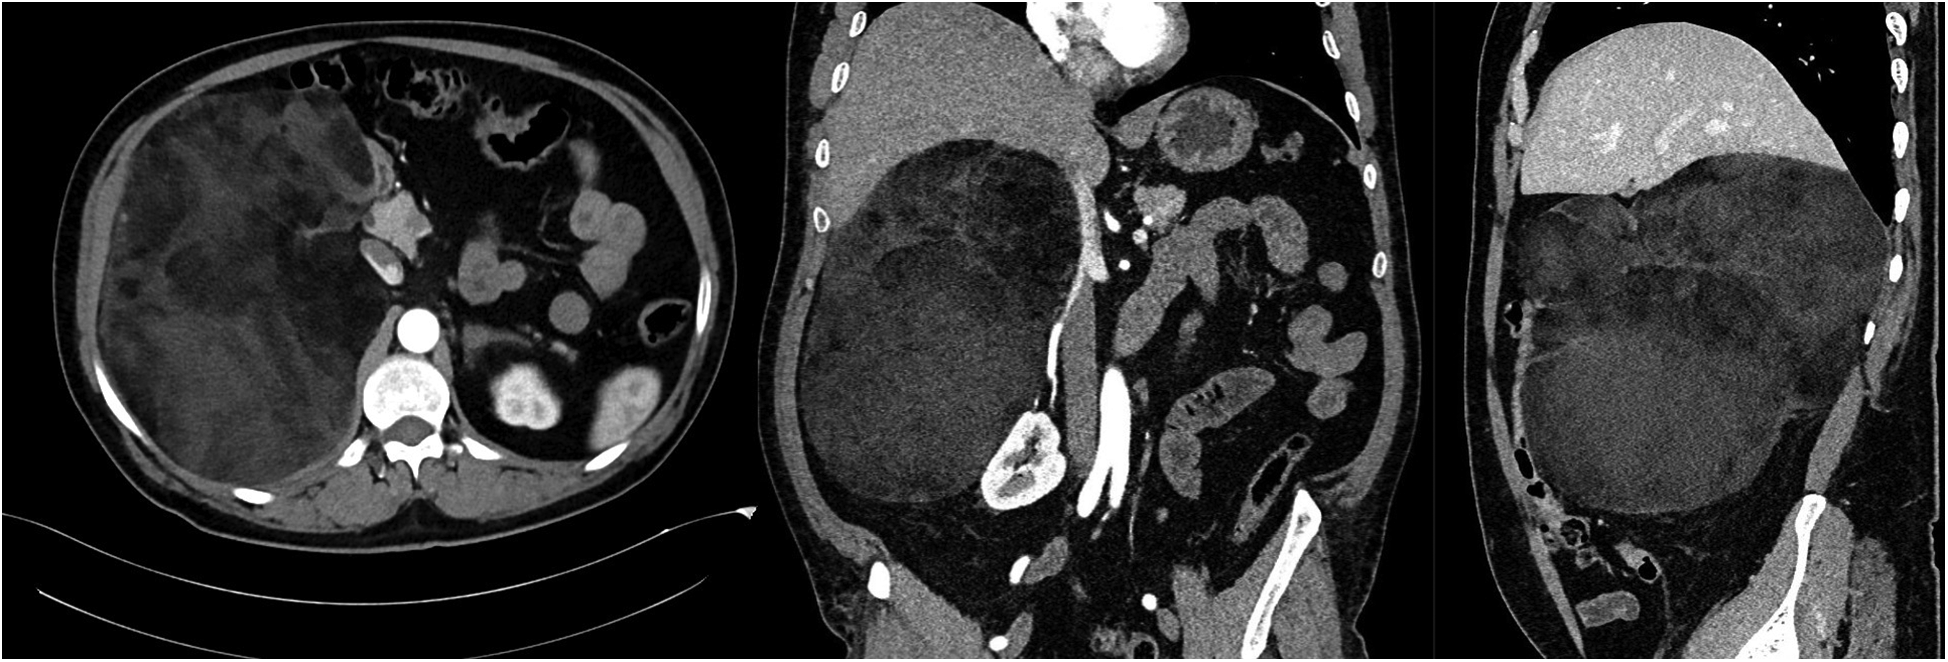

A 53-year-old male patient with no previous medical history was admitted to our hospital's HT clinic with complaints of high blood pressure, accompanied by mild headache and dizziness that had been ongoing for several months. The patient had no other symptoms. The clinical examination revealed a class I obesity with a body mass index of 32.8 kg/m2, a pulse at 78 bpm and high blood pressure of 160/90 mm of Hg in both arms. The average 24 h ABP was 151/91 mm Hg. ECG showed sinus rhythm with a rate of 72 bpm and no abnormalities. TTE did not show left ventricular hypertrophy. A mass was palpated in the right upper quadrant. Abdominal ultrasound revealed a large hyperechoic mass with hypoechoic areas adjacent to the liver. Laboratory studies were normal. 24 h urine catecholamine levels and the rest of the endocrine investigations were normal (Table 1). Abdominal CT revealed a 24 × 16 × 22 cm solid mass with diffuse fat density originating from the right adrenal gland, starting from the left subdiaphragmatic region, extending to the pelvis, and filling the retroperitoneal area (Figure 3). It was causing compression in the inferior vena cava. The patient was diagnosed with adrenal myelolipoma (AML). The patient underwent open surgery, and an encapsulated mass weighing 4,229 g was removed. Histopathological examination reported that the mass contained a mixture of mature adipose tissue and myeloid tissue.

Figure 3

Computed tomography images of a giant right adrenal fatty mass.

After discharge, during the two-year follow-up, the patient had no complaints and did not require any anti-hypertensive medication. Abdominal ultrasound performed at 2 months showed no mass. The average 24 h ABP at three months was 127/81. Home blood pressure monitoring remained normal for two years. An abdominal CT scan performed in the second year of follow-up did not reveal any residual mass (Figure 4).

Figure 4

Computed tomography images at two years postoperatively showing successful resection of a giant adrenal myelolipoma.